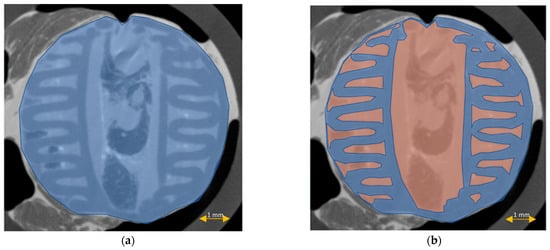

3.6. Scaffold Cross-Sectional Analysis

The scaffold cross-section surface (S1) and soft tissue area inside the scaffold (S2) were marked on the histopathological sections (Figure 9) and μCT images (Figure 10 and Figure 11). Analysis of histopathological sections revealed a tenfold higher STP, introduced as an indicator of scaffold architecture preservation, after the modified protocol compared with after the standard protocol (44.03 ± 1.21 vs. 4.72 ± 0.73). Additionally, the μCT analysis confirmed better scaffold architecture preservation after the modified procedure compared with the standard histopathological procedure. The STP calculated on the μCT images after the modified procedure was only 2.5% lower compared with the images obtained before the procedure (43.34 ± 1.59 vs. 45.76 ± 1.29). In contrast, after the standard procedure, the STP was ninefold lower than before the procedure (5.23 ± 2.30 vs. 45.23 ± 1.19).

Figure 9.

Scaffold cross-section surface (S1, blue) and soft tissue area inside the scaffold (S2, orange) on sections obtained after the standard histopathological (a,b) and modified histopathological protocols (c,d).